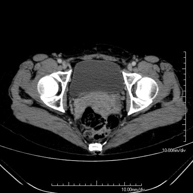

- TC Pelvis Prueba diagnóstica que consiste en obtener imágenes bi y tridimensionales de la pelvis de alta definición anatómica (estructuras óseas, estructuras vasculares, vejiga, útero y ovarios, próstata y vesículas seminales, uréteres, etc.) mediante el empleo de un equipo de TC (Tomografía Computarizada). La mayoría de estudios requieren el empleo de contraste yodado. Prueba diagnóstica que consiste en obtener imágenes bi y tridimensionales de la pelvis de alta definición anatómica (estructuras óseas, estructuras vasculares, vejiga, útero y ovarios, próstata y vesículas seminales, uréteres, etc.) mediante el empleo de un equipo de TC (Tomografía Computarizada). La mayoría de estudios requieren el empleo de contraste yodado.

- TC Pelvis ósea Exploración radiológica que mediante un sistema de rayos X y detectores que giran alrededor del paciente, reconstruyendo las imágenes por ordenador (TC Multidetector), permite el estudio de huesos, músculos y articulaciones de la pelvis. Exploración radiológica que mediante un sistema de rayos X y detectores que giran alrededor del paciente, reconstruyendo las imágenes por ordenador (TC Multidetector), permite el estudio de huesos, músculos y articulaciones de la pelvis.